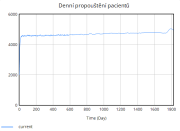

| 22:34, 15 June 2025 | 1 Propouštění.png (file) |  |

11 KB | Kozo01 | 1 | |